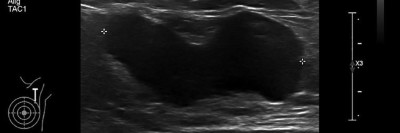

CT-Befund des Thorax/© Prof. A.- J. Lemke, Zentrum für Radiologie, Gesundheit Nord gGmbH, Bremen, mit freundlicher Genehmigung , Koloskopie/© Kzenon / stock.adobe.com (Symbolbild mit Fotomodellen), Thrombozytopenie/© Kreipe, H. / all rights reserved Springer Medizin Verlag GmbH, Echoarmen Lymphknotenmetastase ohne Mark-Rinden-Struktur im Ultraschall/© Wihlfahrt K et al. / all rights reserved Springer Medizin Verlag GmbH, Patientin schaut besorgt auf Infusionsbeutel/© KatarzynaBialasiewicz / Getty Images / iStock (Symbolbild mit Fotomodellen), Zytologie mit Plasmazellen/© David A Litman / stock.adobe.com, Mit Schuhen auf Körperwaage/© Africa Studio / Stock.adobe.com (Symbolbild mit Fotomodell), Histopathologischer Befund bei akuter myeloischer Leukämie/© National Cancer Institute/cancer.gov, Einer Frau wird eine Infusion gelegt/© stephm2506 / stock.adobe.com, Röntgenassistentin bedient Röntgengerät/© nicoletaionescu / Stock.adobe.com (Symbolbild mit Fotomodell), Frau hält Kapseln in der Hand/© diego cervo / stock.adobe.com, Kraniales MRT/© Dr. Müller-Abt, Kinderradiologie, Olgahospital Stuttgart (Mit freundl. Genehmigung, alle Rechte vorbehalten), Search Icon, Blutabstrich der chonisch lymphatischen Leukämie/© jarun011 / Getty Images / iStock, Endoskopische Befunde des Magenkarzinoms/© Probst, A., Messmann, H. / all rights reserved Springer Medizin Verlag GmbH, Hand hält Laborröhrchen/© Kunstzeug / stock.adobe.com (Symbolbild mit Fotomodell), Radiologin richtet Mammographiescreening ein/© LIGHTFIELD STUDIOS / stock.adobe.com (Symbolbild mit Fotomodellen)